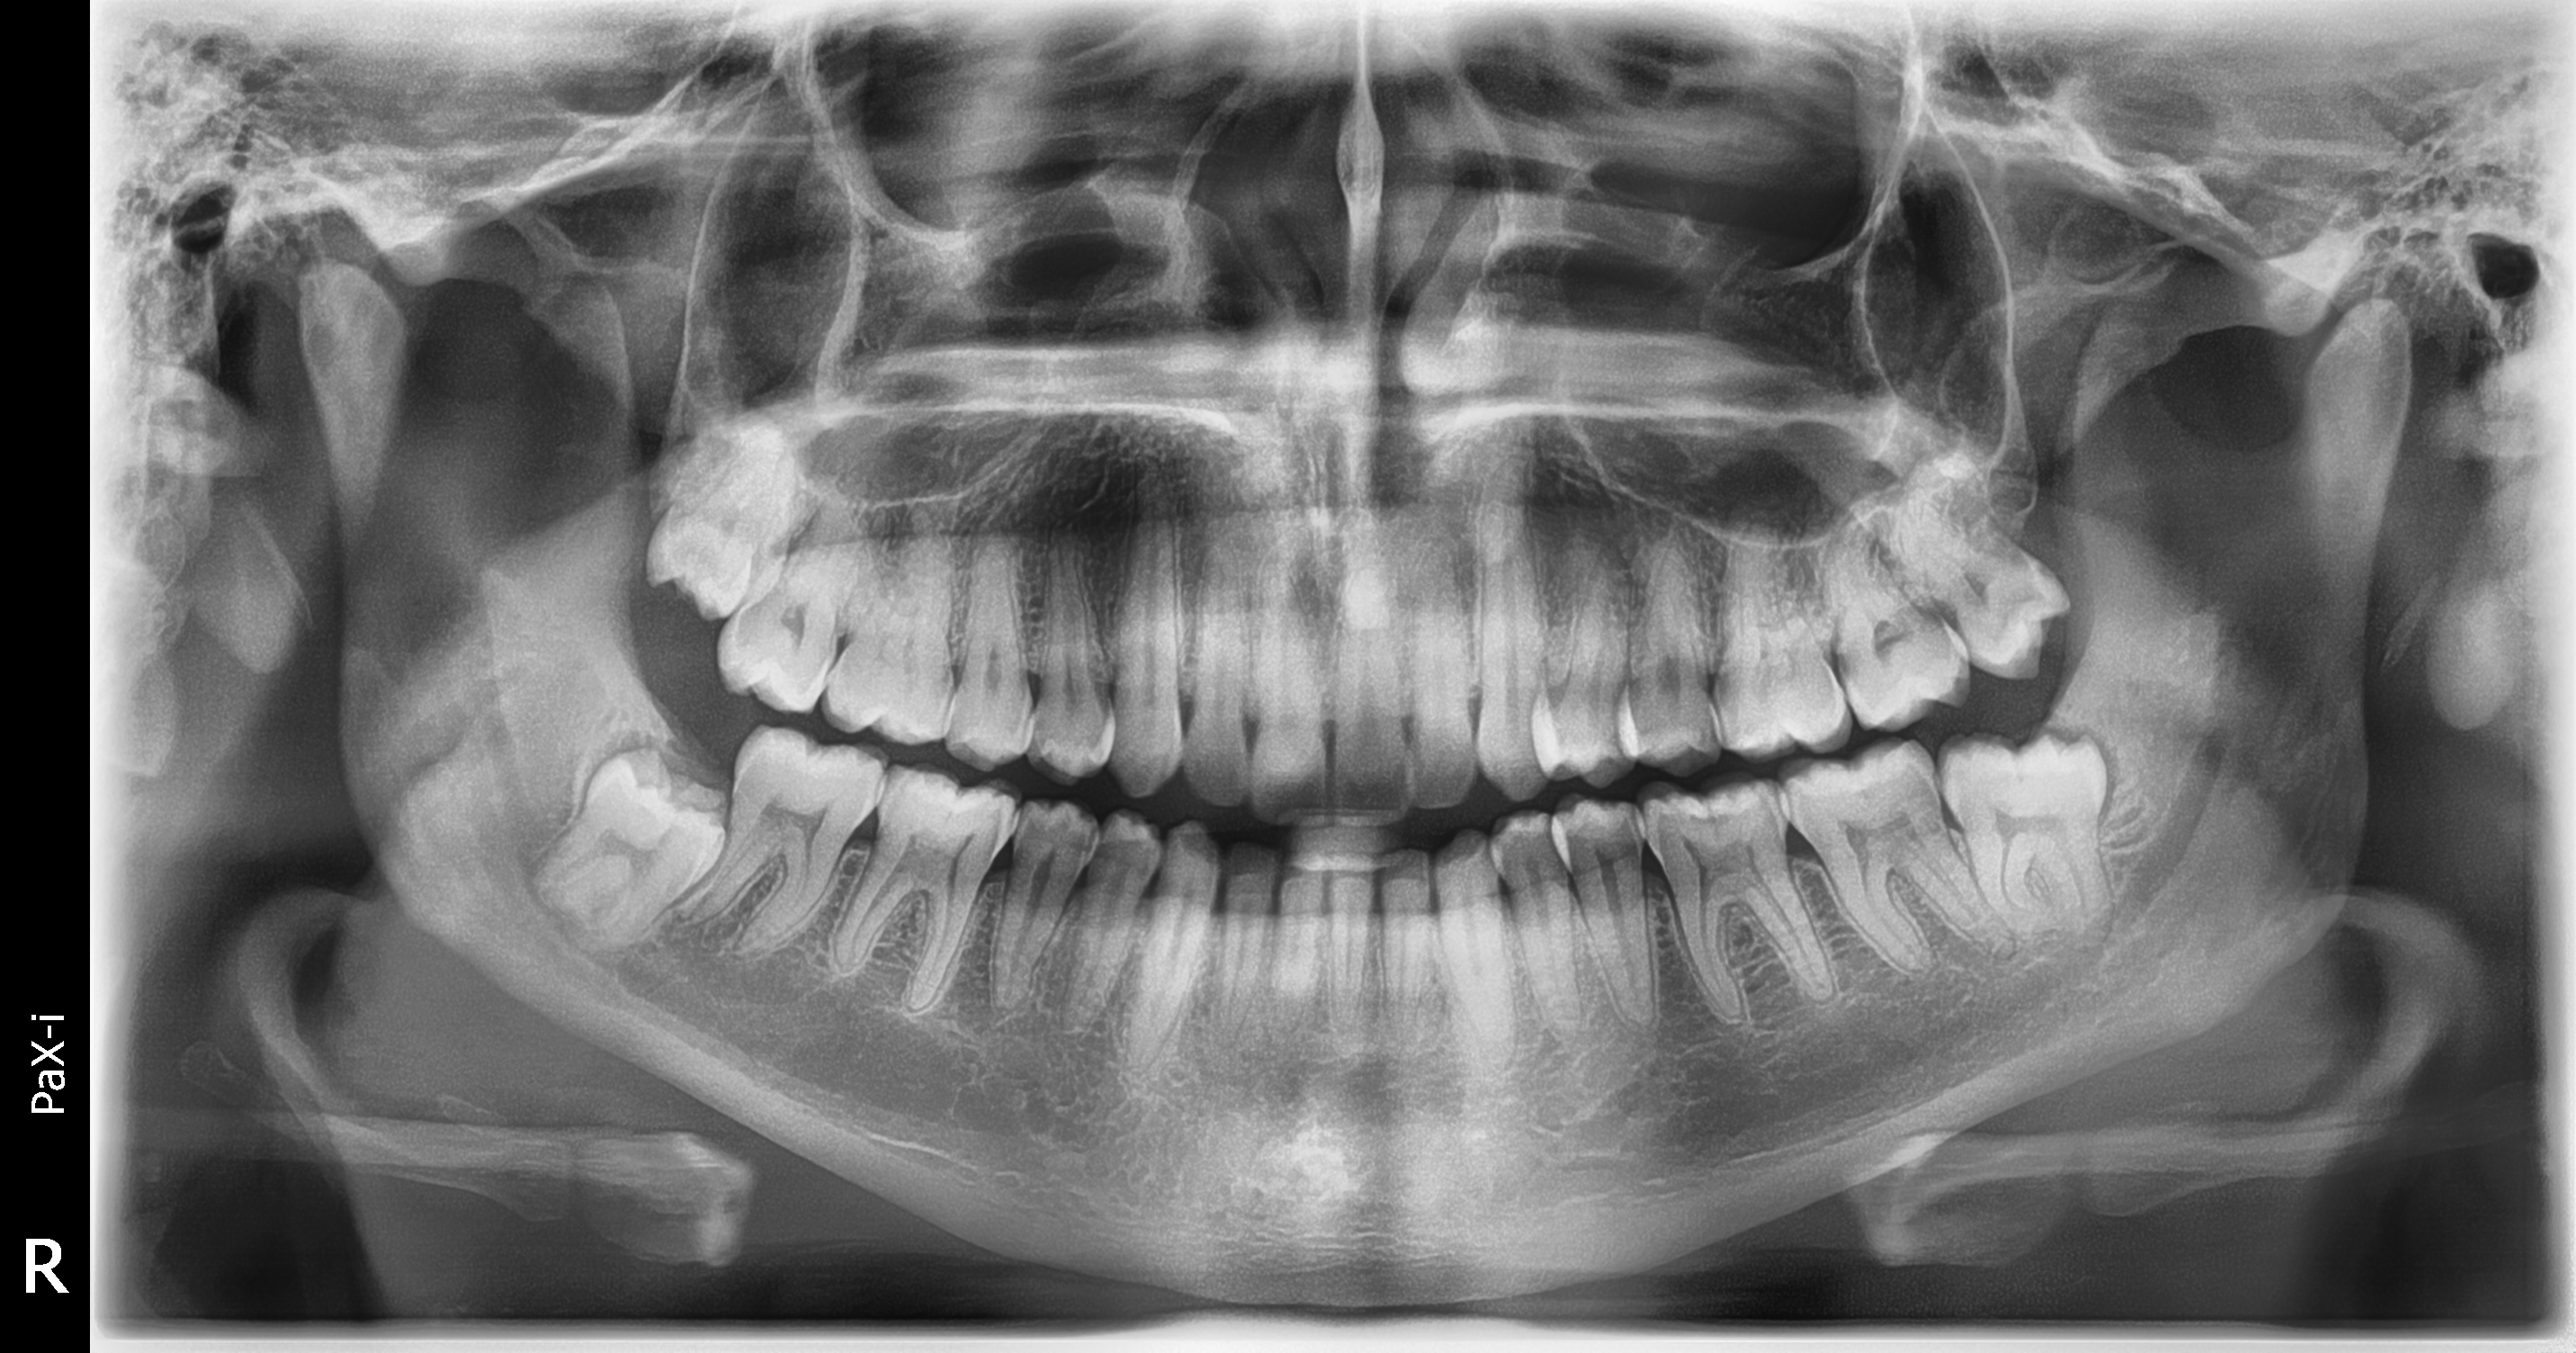

Gracias al Dr. WILMER CERNA, por seguir confiando en nosotros y adquirir su nuevo equipo. Centro ubicado en Carabayllo, instalación de equipo PaX-i SC (Panorámico/Cefalometrico) de la marca VATECH.